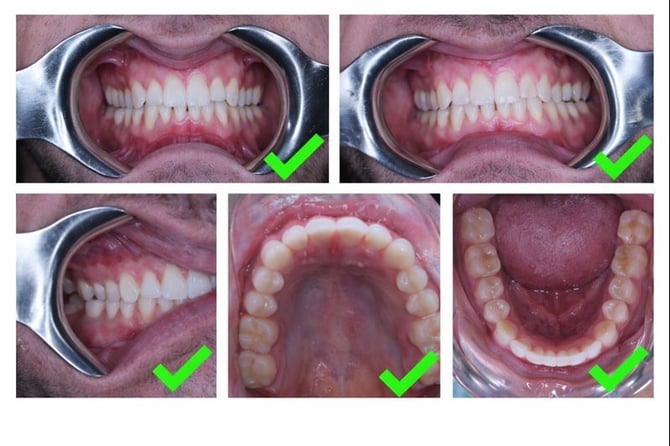

Clinical photos

-

Arch photos (≤ 1 year)

Used to assess:-

Wear and erosion

Gingival recession

Alignment and spacing

Upper, lower, and lateral views help ensure complete coverage.